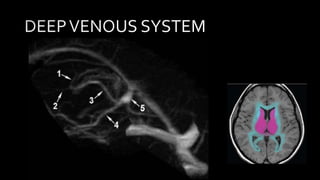

• #129 MIP image from CE MR venography with color overlay shows Lateral MIP images from CE MR V shows veins from the lateral cerebral hemisphere that drains into the SSS 1 frontopolar , 2 anterior frontal , 3 posterior frontal , 4 vein ot tolard , 5 anterior parietal 6 SMCV which drain into sphwenopartietal snus or cavernous sinus , 7 is the vein of labbe that drains into transverse sinus

• #130 These are the Axial color coded diag demonstrating venous draignage pattern. As we can see Most of the Superficial part of the brain ie. Cortex , subcortical white matter shown in green color atre drained by cortical vein ( including VOT) and sss. Central core brain structures ie basal ganglia , thalami , lat and 3rd ventricles and most of corona radiate are drained by deep venous system ie. ICB , VOG & SS. Transverse sinus and vein of labbe drain the posterior temporal and inferior parietal lobe as shown in yellow color . Sp and cv

• #131 Lateral MIP image from CE MRV shows major component of deep venous system. 1 is the thalamostraite vein , 2 is septal vein 3rd is the internal cerebral vein , 4 is the basal vein of Rosenthal 5 th is the VOG